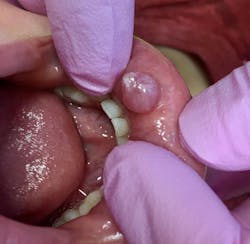

At a six-month checkup, the patient's chief complaint was a large sore on the lower lip that was described as: “comes and goes.” His mom said: "He will bite the bubble and it pops with lots of liquid, but it grows again."

Clinical assessment on the lower lip revealed:

- 7 mm-plus soft, exophytic, dome-like lesion

- Normal lip color

- Fluid filled with a slightly red base

- No pain, but the patient was having a hard time eating due to position and size of lesion